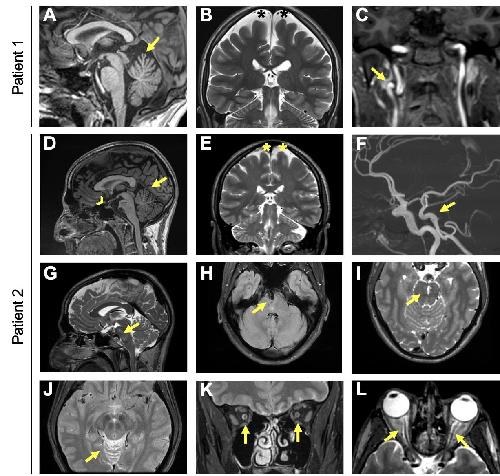

TBC1D32 variants disrupt retinal ciliogenesis and cause retinitis pigmentosa., Bocquet B, Borday C, Erkilic N, Mamaeva D, Donval A, Masson C, Parain K, Kaminska K, Quinodoz M, Perea-Romero I, Garcia-Garcia G, Jimenez-Medina C, Boukhaddaoui H, Coget A, Leboucq N, Calzetti G, Gandolfi S, Percesepe A, Barili V, Uliana V, Delsante M, Bozzetti F, Scholl HP, Corton M, Ayuso C, Millan JM, Rivolta C, Meunier I, Perron M, Kalatzis V., JCI Insight. November 8, 2023; 8 (21):